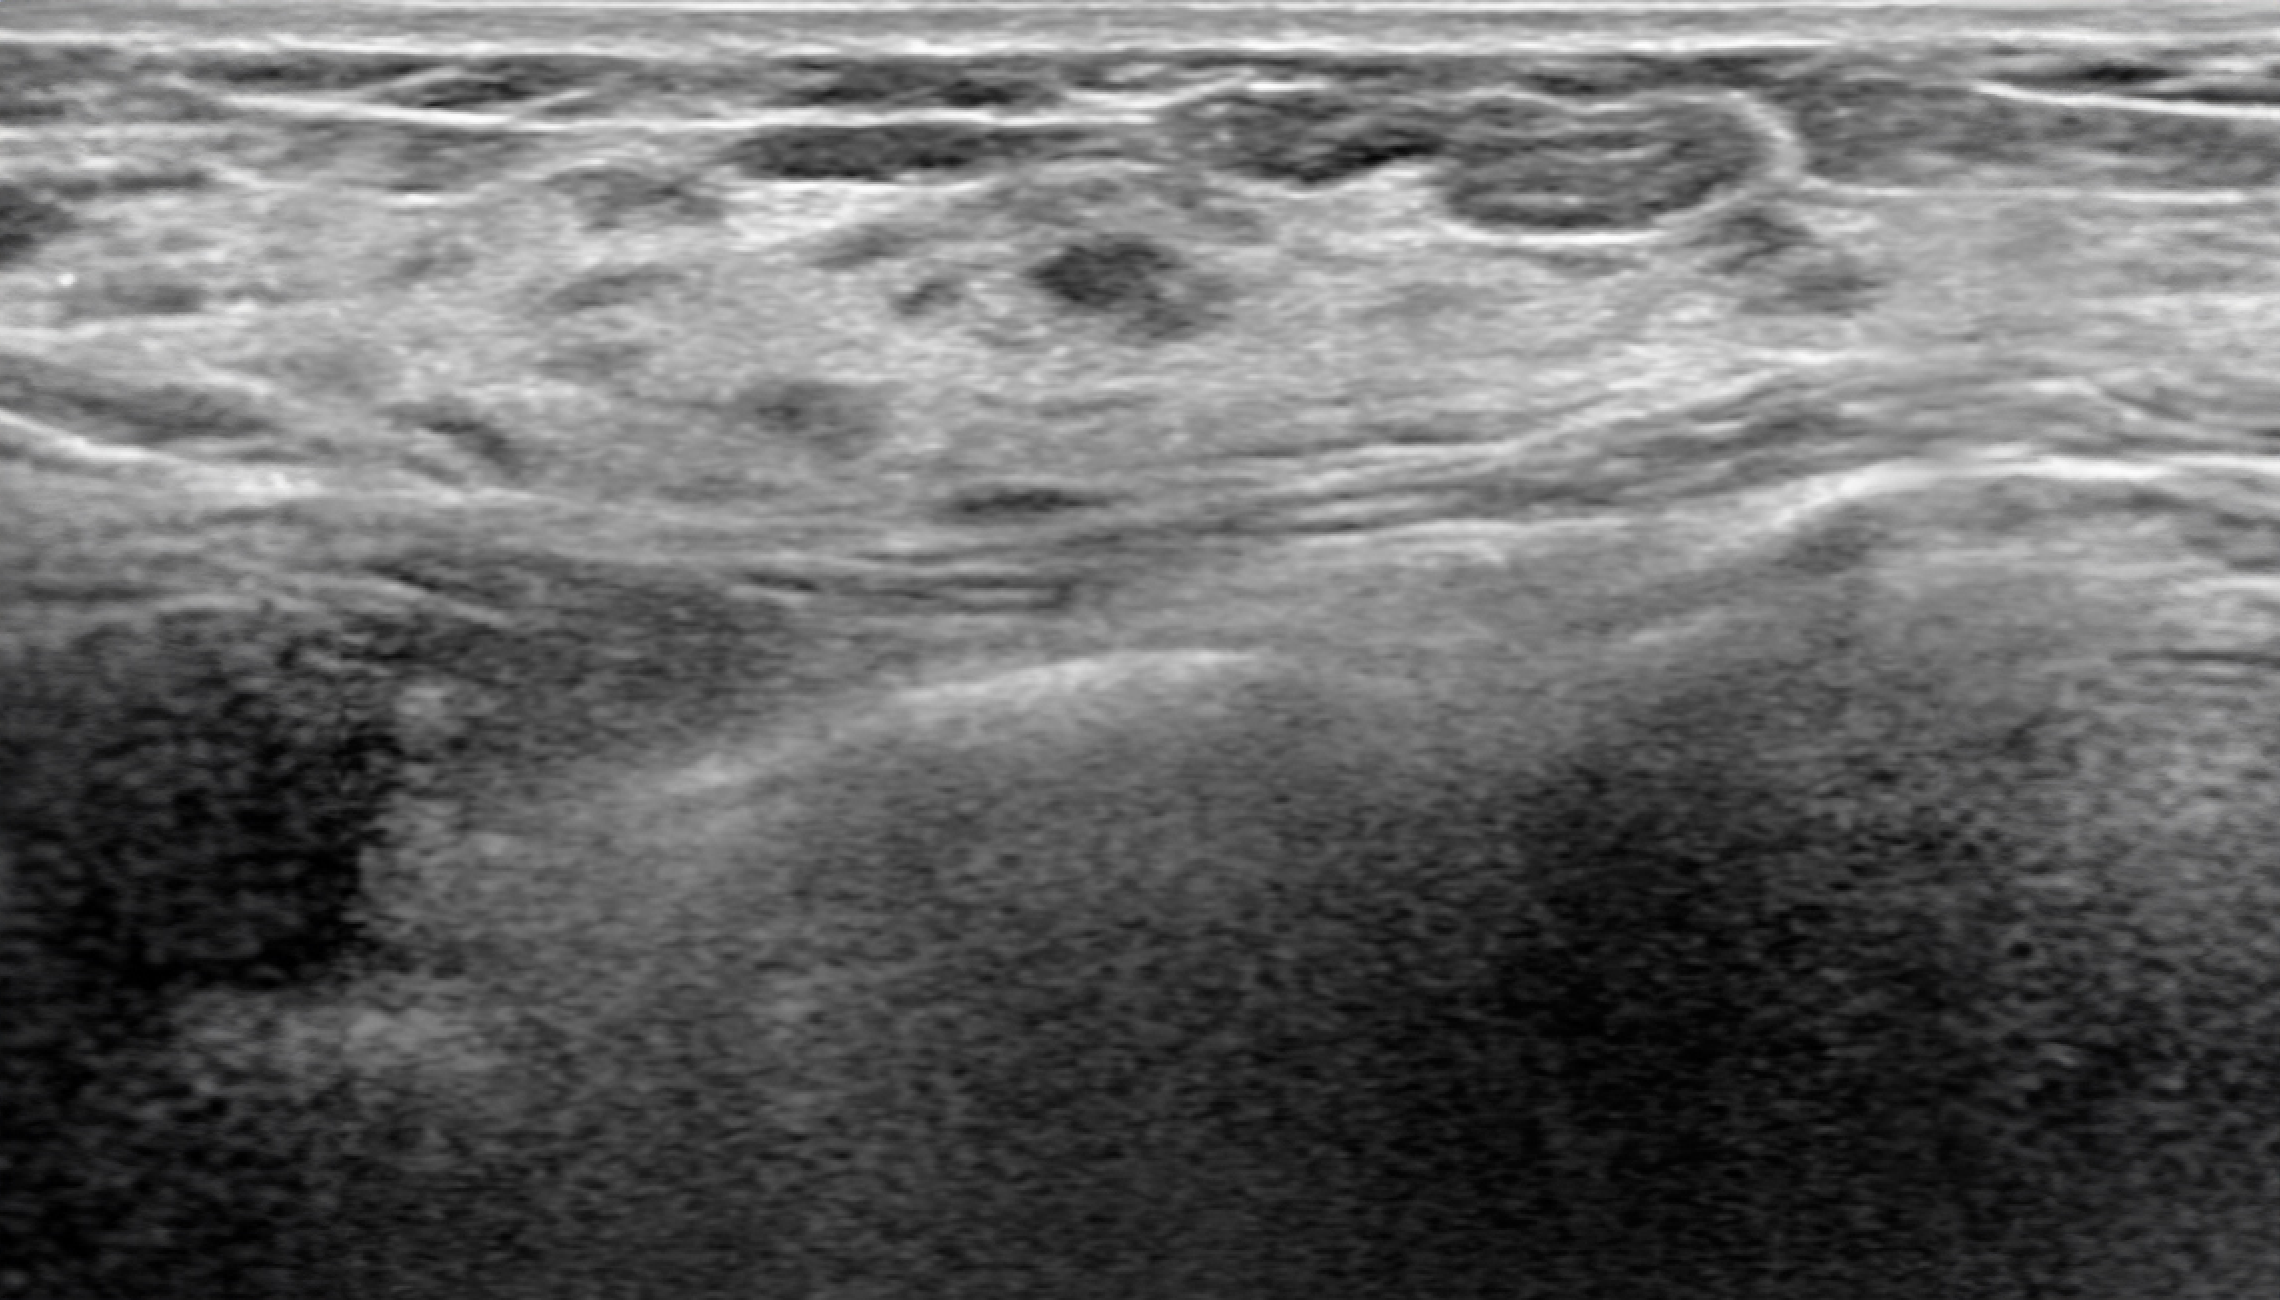

Follow up mode

Automatically matches lesions from previous breast ultrasound examinations, allowing for easy comparison of changes in the lesions.